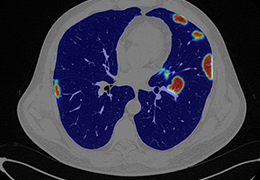

成像智能。

Eclipse 成像智能功能提供强大的处理能力和最佳质量的影像,同时减少质量错误并提高剂量效率。

凭借 AI、专有算法和先进的影像处理能力,提供出色的影像质量和无与伦比的诊断信心。

与标准影像处理相比,智能降噪功能可使客户降低辐射剂量,而不会损失影像质量。这在新生儿和儿科成像中尤其重要,在这种情况下以尽可能低的剂量成像至关重要。